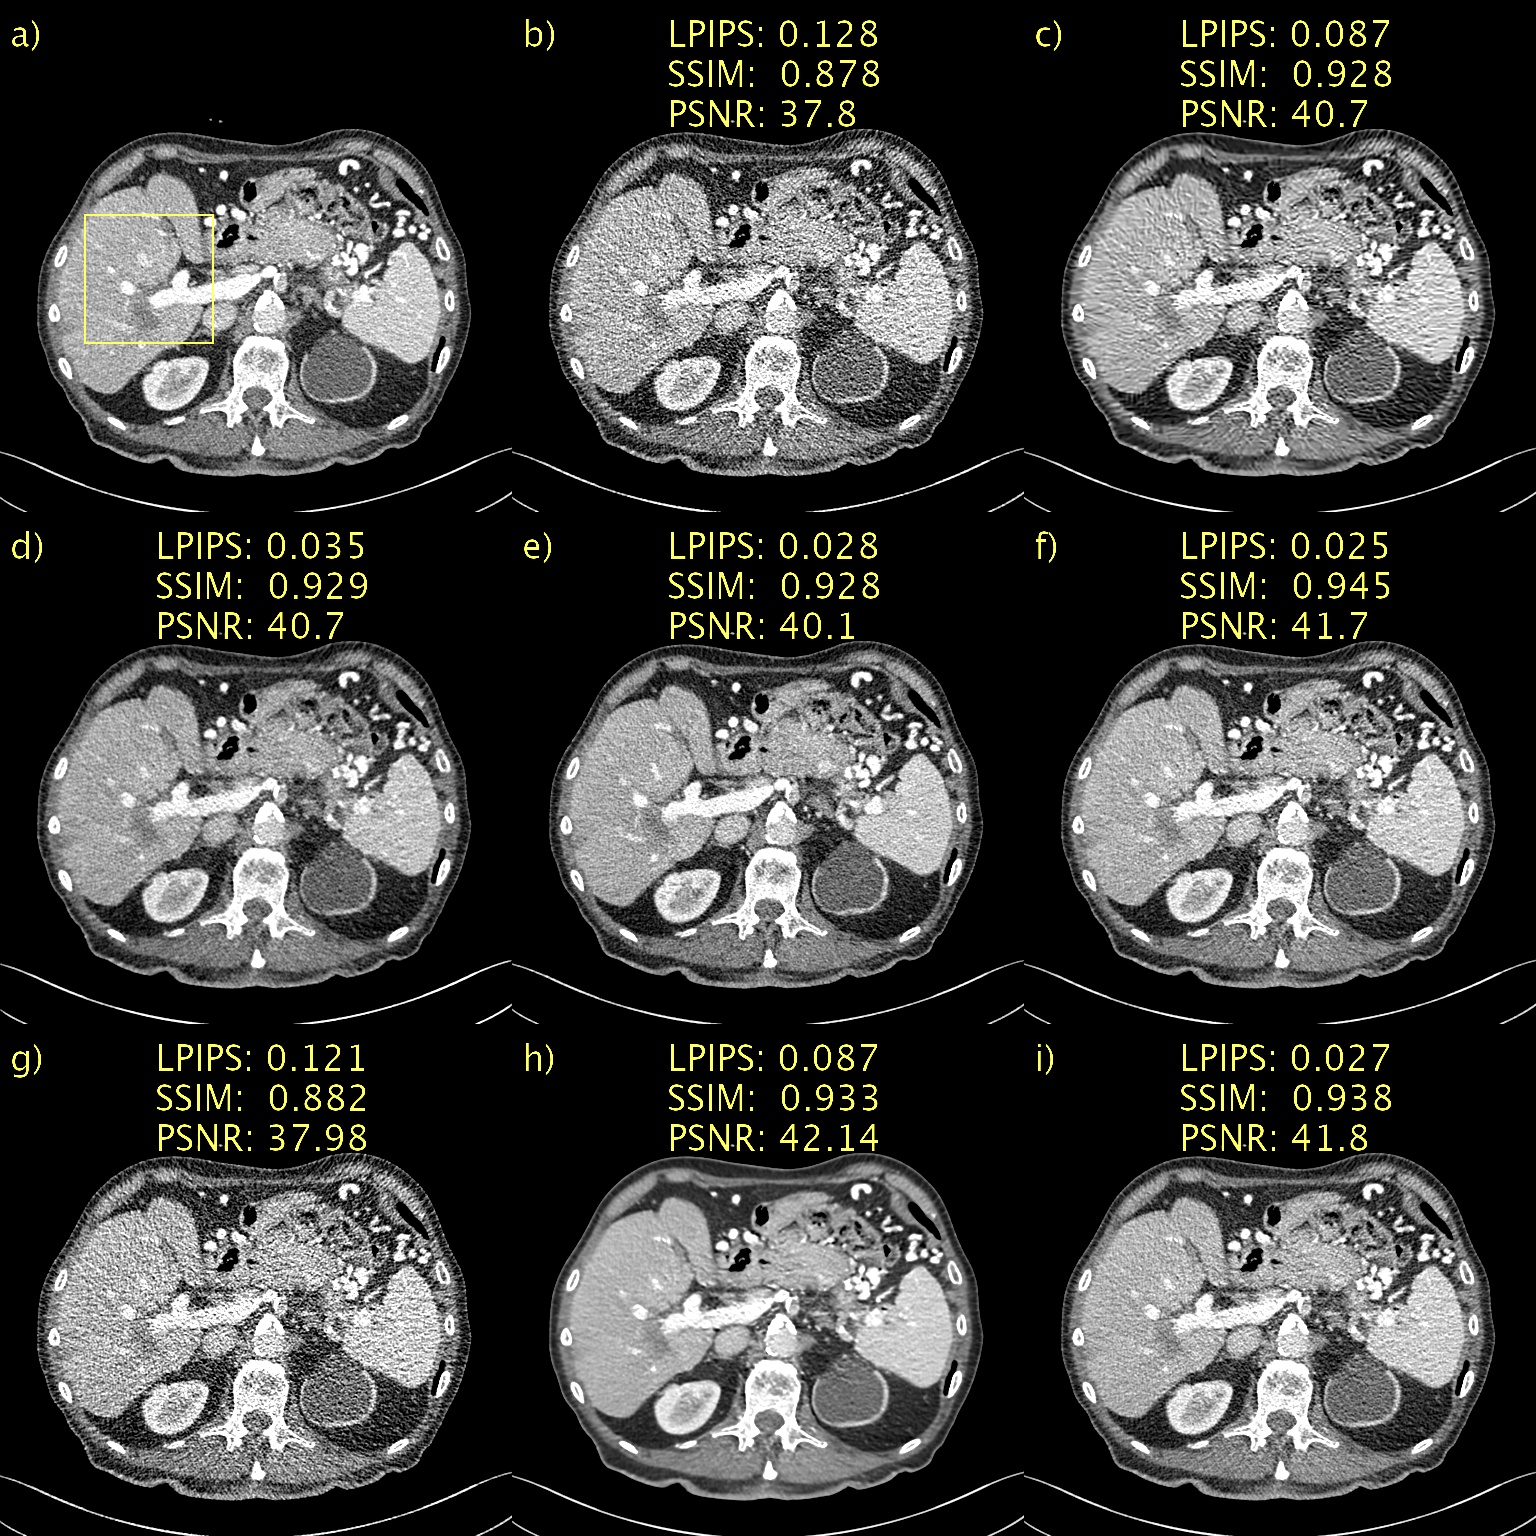

Qualitative results, alongside LPIPS, SSIM, and PSNR, for a representative slice from the Mayo low-dose CT validation data appear in Fig. 1. For the sake of brevity, we show results for the proposed method only for D𝐷D\rightarrow\infty and, best performing, D=128.𝐷128D=128. The former is included as an interesting case since it corresponds to a diffusion model, instead of PFGM++. This patient has a metastasis in the liver and we have included a magnification of this region of interest (ROI) in Fig. 2. a) and b) show the NDCT and LDCT images, respectively for reference. BM3D, shown in c), performs well in terms of noise suppression whilst preserving salient details. Nevertheless, this comes at a cost of artifacts that make the image appear a somewhat smudgy. WGAN-VGG, CD, and PPFM, all supervised methods, shown in d), e) and f), all suppress noise effectively and keep key details intact. We have overlaid a yellow arrow to point out a detail that appears in CD, shown e), but in none of the other images, including NDCT and LDCT. It appears that CD has added a feature into the image that appears realistic, but which we know is not genuine, given that we have the LDCT and NDCT images as reference. Such inaccurate removal or addition of details is loosely referred to as hallucination [2]. Noise2Void, shown in g), seems to in essence reproduce the LDCT image. However, quantitatively there is a marginal improvement. However, as shown in i), the proposed method (with D=128𝐷128D=128) effectively suppresses the noise whilst keeping salient features intact. Qualitatively, it is difficult to discriminate between the proposed method with D=128,𝐷128D=128, which is an unsupervised method, and PPFM, shown in f), a supervised method. Quantitatively for this particular slice, we can see that PPFM performs slightly better. Comparing D𝐷D\rightarrow\infty, shown in h), with D=128𝐷128D=128 in i) demonstrates the performance gains afforded by the PFGM++ framework. In particular, the proposed method with D𝐷D\rightarrow\infty appears over-smoothed and somewhat blurred.

Figure 1: Results on the Mayo low-dose CT dataset. Abdomen image with a metastasis in the liver. a) NDCT, b) LDCT, c) BM3D, d) WGAN-VGG, e) CD, f) PPFM, g) Noise2Void h) D𝐷D\rightarrow\infty i) D=128𝐷128D=128. Yellow box indicating ROI shown in Fig. 2. 1 mm-slices. Window setting [-160,240] HU.

Figure 2: ROI in Fig. 1 magnified to emphasize details. a) NDCT, b) LDCT, c) BM3D, d) WGAN-VGG, e) CD, f) PPFM, g) Noise2Void h) D𝐷D\rightarrow\infty i) D=128𝐷128D=128. Yellow circle added to emphasize lesion. 1 mm-slices. Window setting [-160,240] HU.